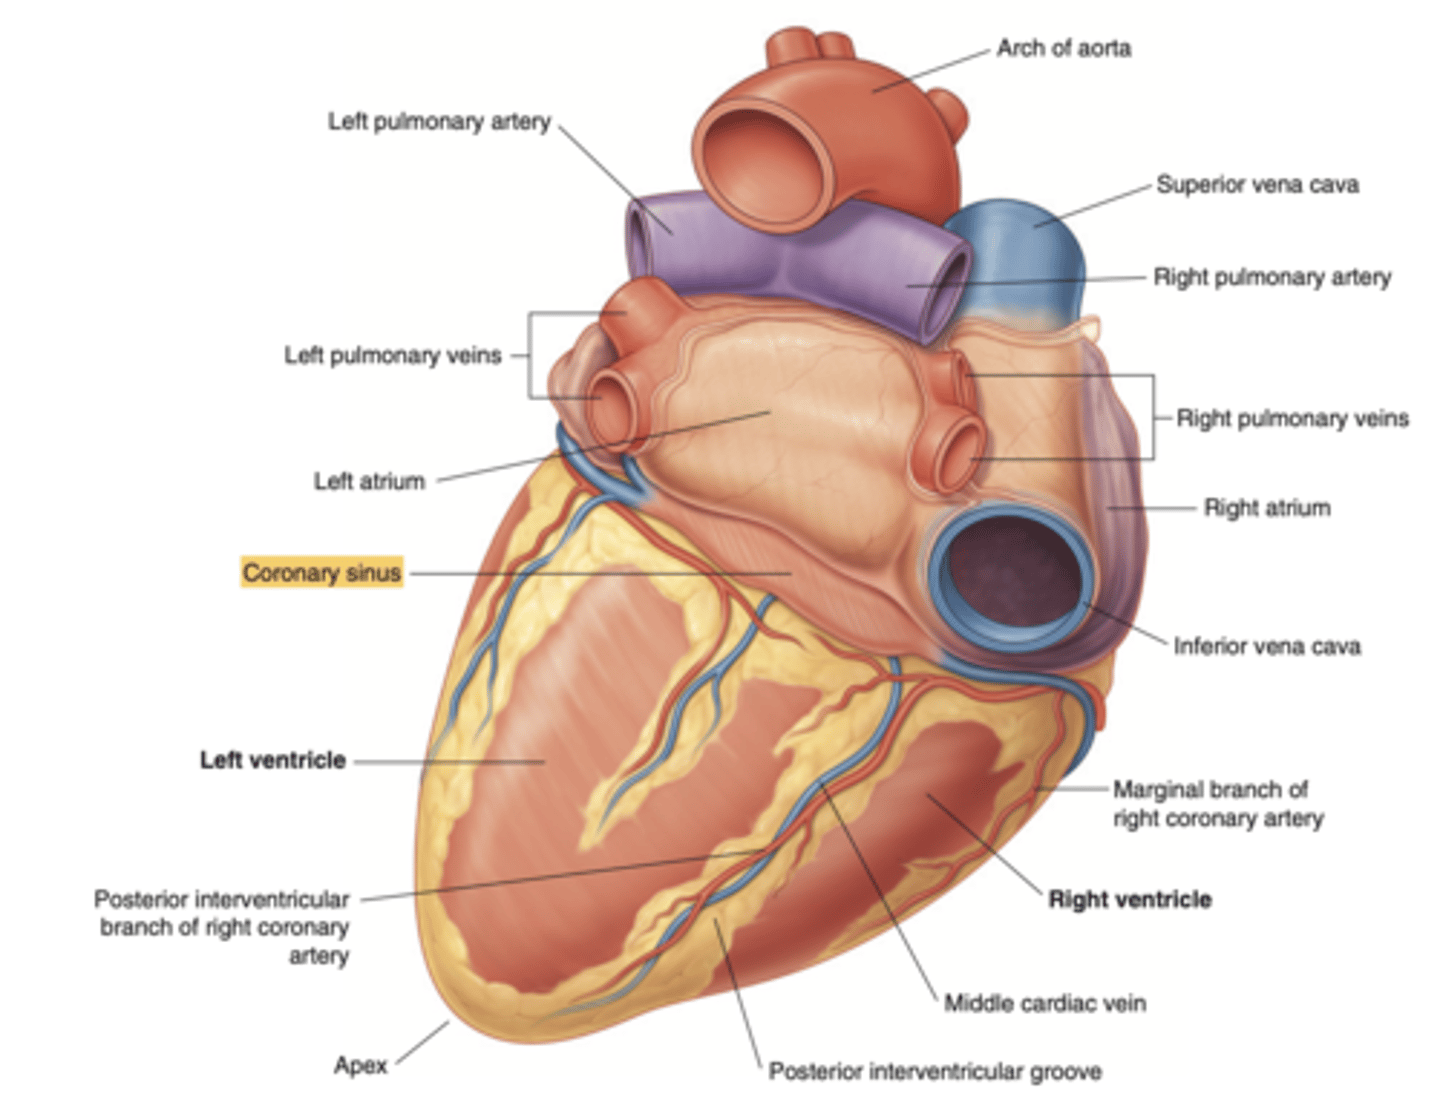

Show the position of the coronary sinus in the posterior view of the heart and its function

collects deoxygenated blood from most of the heart's venous system

delivers it to the right atrium for reoxygenation.

Show the position of the ventricles and auricles in the posterior view

Which veins enter the left atrium?

left pulmonary veins

right pulmonary veins

ALLOWS OXIGENATED BLOOD FROM THE LUNGS TO ENTER THE HEART